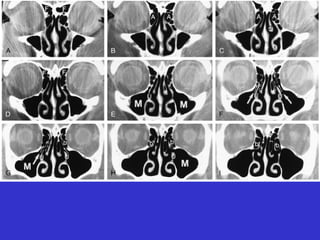

Este documento describe las diferentes proyecciones radiográficas utilizadas para examinar los senos paranasales, incluyendo las proyecciones básicas de Caldwell, Waters lateral y las proyecciones especiales como Hirtz y Waters mentonasal. También describe las diferentes estructuras anatómicas que componen el complejo ostiomeatal anterior y posterior de los senos paranasales.